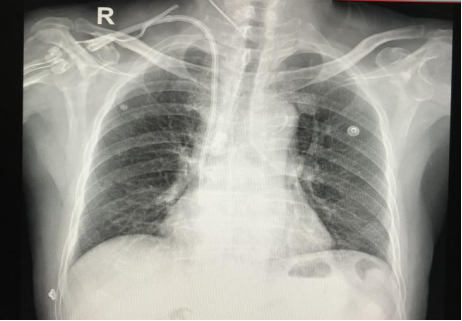

手术由肾病科副主任医师张馨予主刀,与助手田甜医师一起,为其实施了带cuff的半永久透析导管置入术,手术顺利,术后应用此导管进行血液透析,血流量充足,透析效果良好。

带Cuff的中心静脉导管是将特制的带涤纶套埋于皮下隧道,导管入颈内静脉,到达上腔静脉至右心房交界处而建立的血管通路。其优点为插入后即可使用,无血流动力学紊乱,无需长期多次内瘘静脉穿刺痛苦,较临时导管感染率低等。